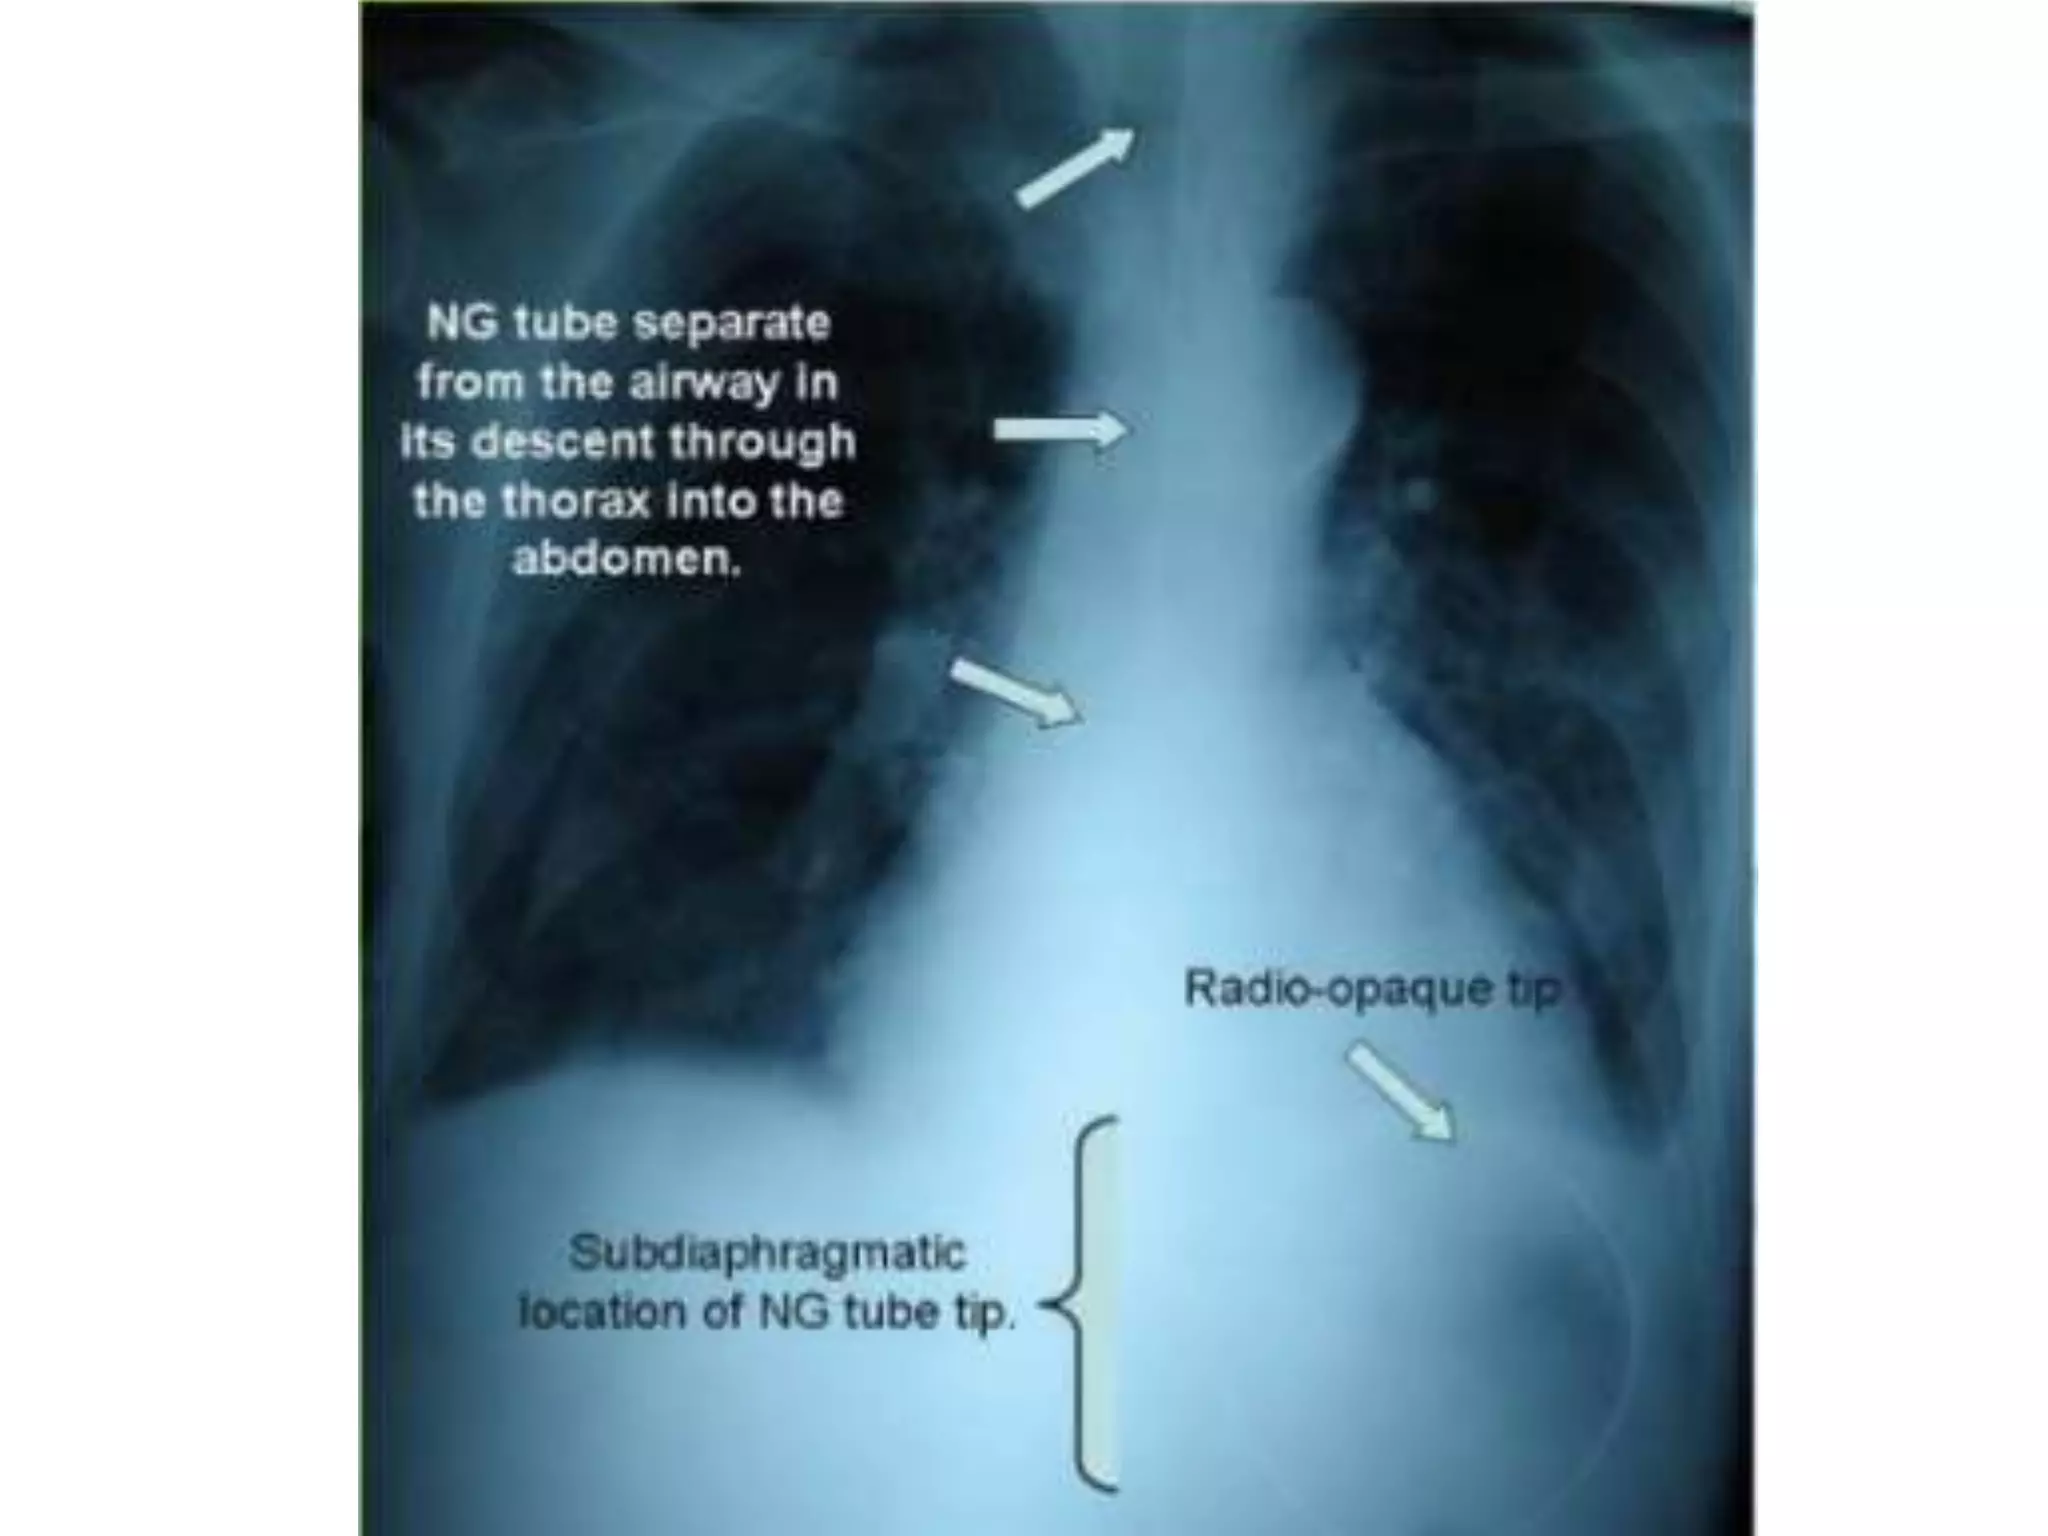

This document provides instructions for inserting and removing a nasogastric tube. It was presented by an associate professor and head of the department of medical surgical nursing. The document outlines the necessary equipment, provides step-by-step instructions for insertion and removal of the tube, and concludes the presentation.